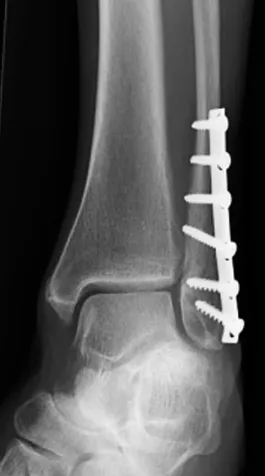

內固定手術:通過外科手術將腓骨斷端重新排列,然後使用釘子、螺釘、金屬板等內部固定物將骨骼部位固定在一起。